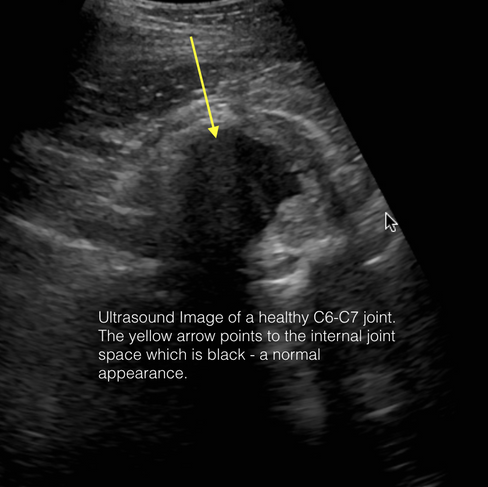

Ultrasonography is highly useful for evaluating the soft tissues of the joints. It allows for side-by-side comparisons, assesses joint fluid and surrounding structures, and facilitates targeted treatment through ultrasound-guided injections.